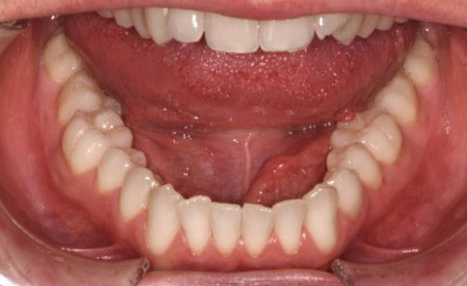

A 38-year-old male patient sought orthodontic treatment with both functional and esthetic concerns. His main complaints included the appearance of an inverted smile arc, reduced incisor display, and a general lack of harmony in his smile.

The extraoral examination revealed a long facial type with an increased lower facial third, nasolabial folds accentuated by insufficient midface support, and broad buccal corridors due to maxillary compression. Intraoral analysis showed a posterior crossbite, negative torque on posterior teeth, and an altered occlusal balance. Radiographic and cephalometric evaluation confirmed the clinical findings, with an increased mandibularplane angle and mandibular posterior rotation. This rotation contributed to a convexity of +4 mm, although the underlying problem was a retruded maxilla with insufficient midface support. Vertical facial height was also increased. Importantly, the temporomandibular joint evaluation showed a posterior condylar position with intact cortical bone, no pain, and no joint sounds.

(Images: Intraoral Initial)